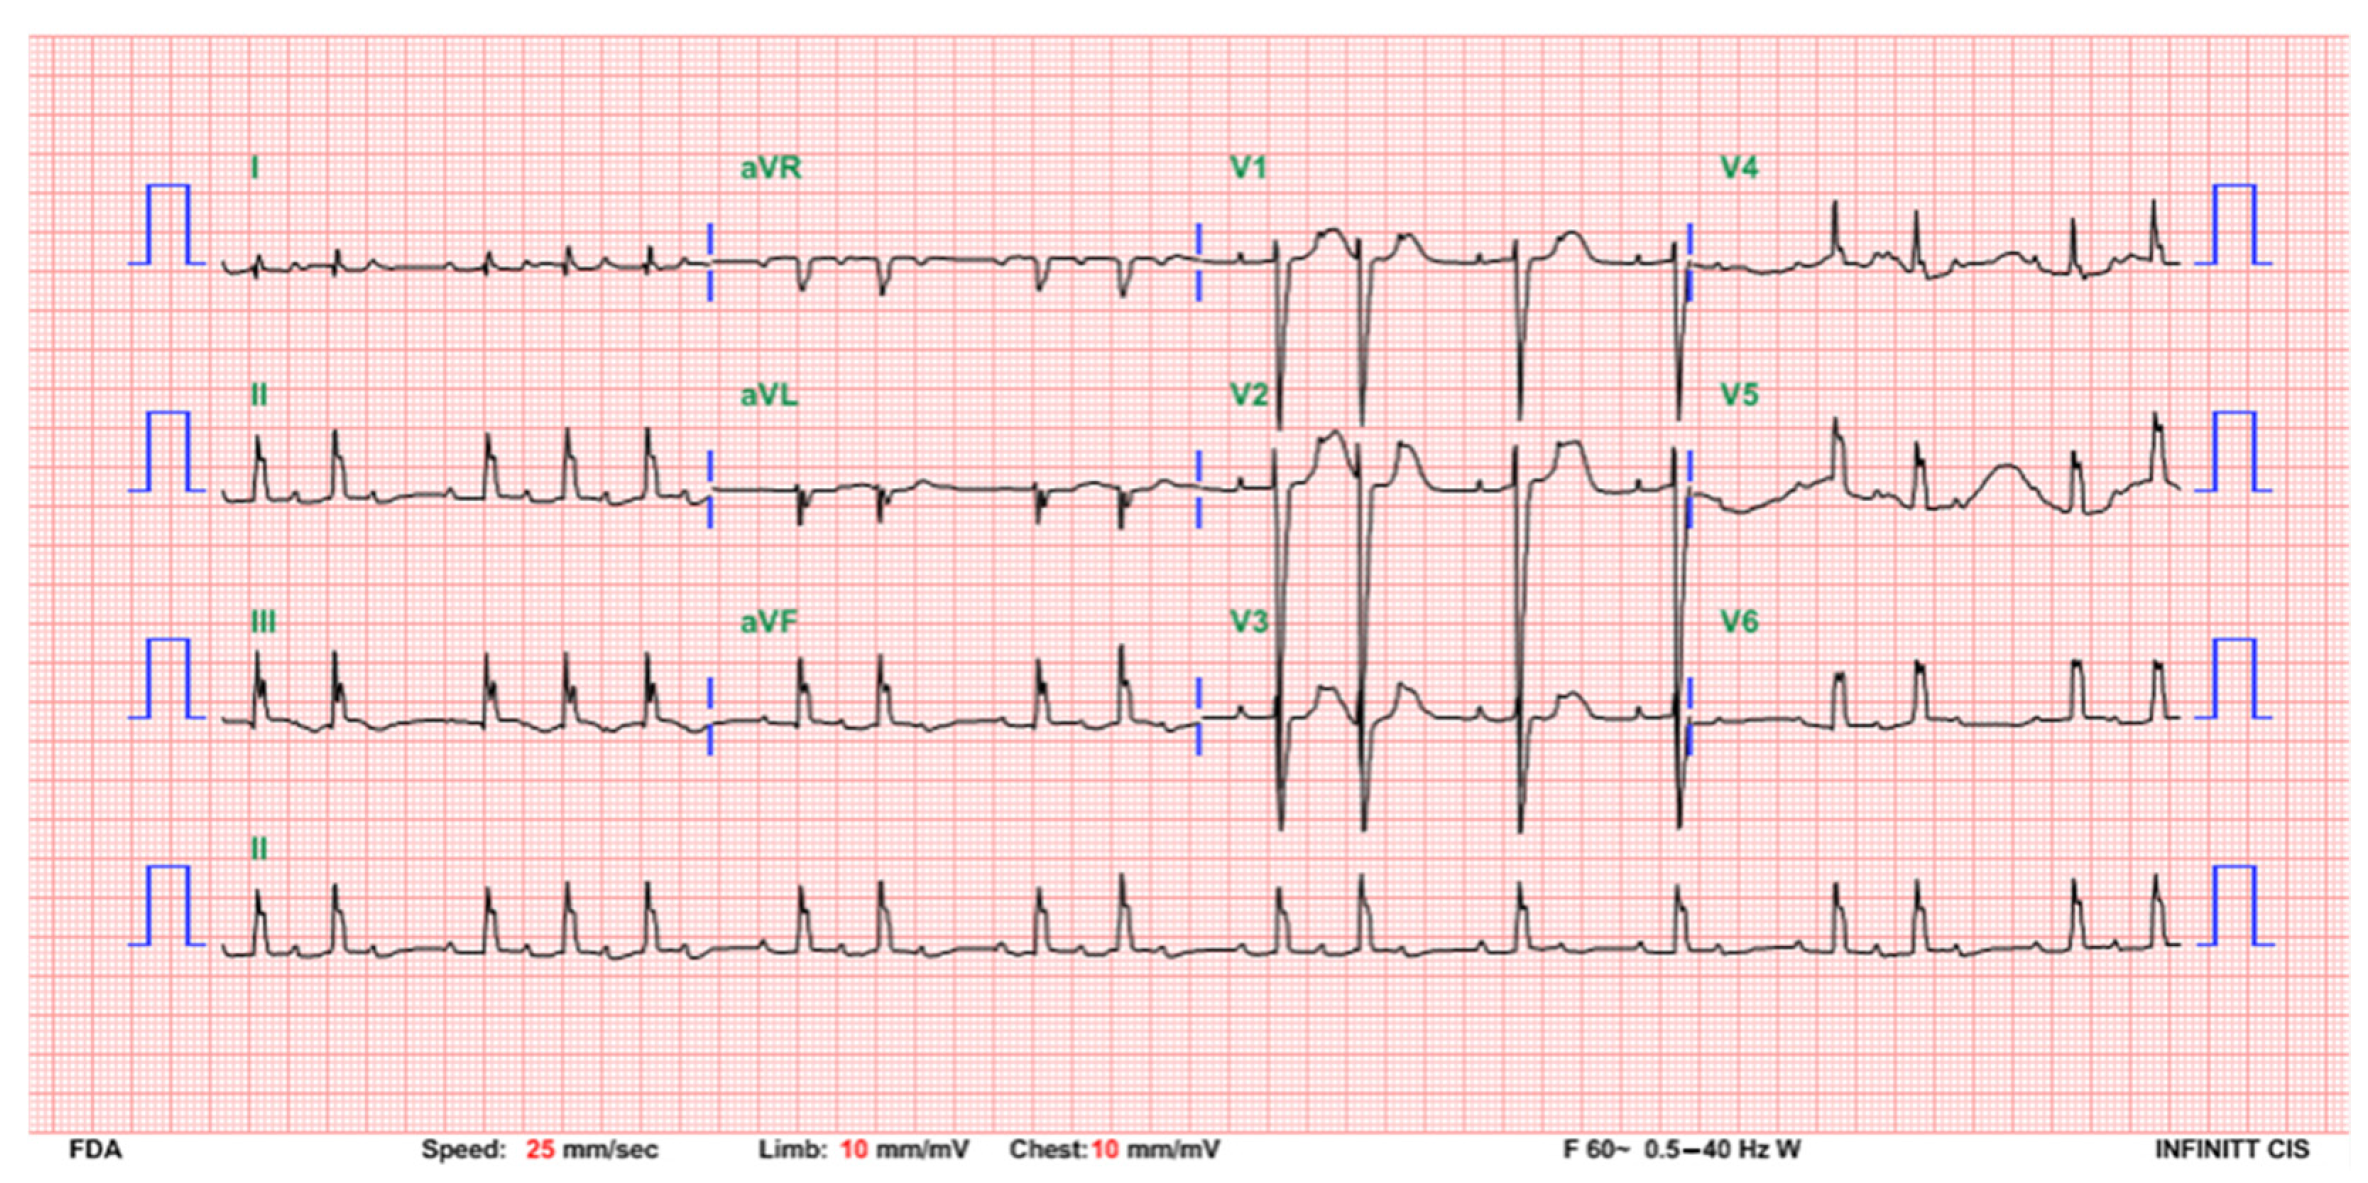

2. Case Presentation